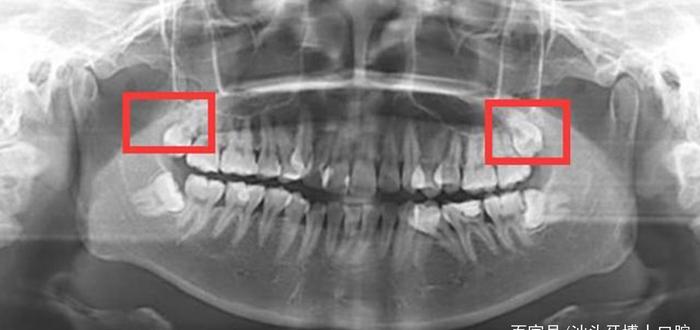

另外,有些智齿不能正常萌出,埋在牙龈下面,从口腔外部是看不出来的,只有拍摄口腔CT才能看到,这也会被误以为是不长智齿。